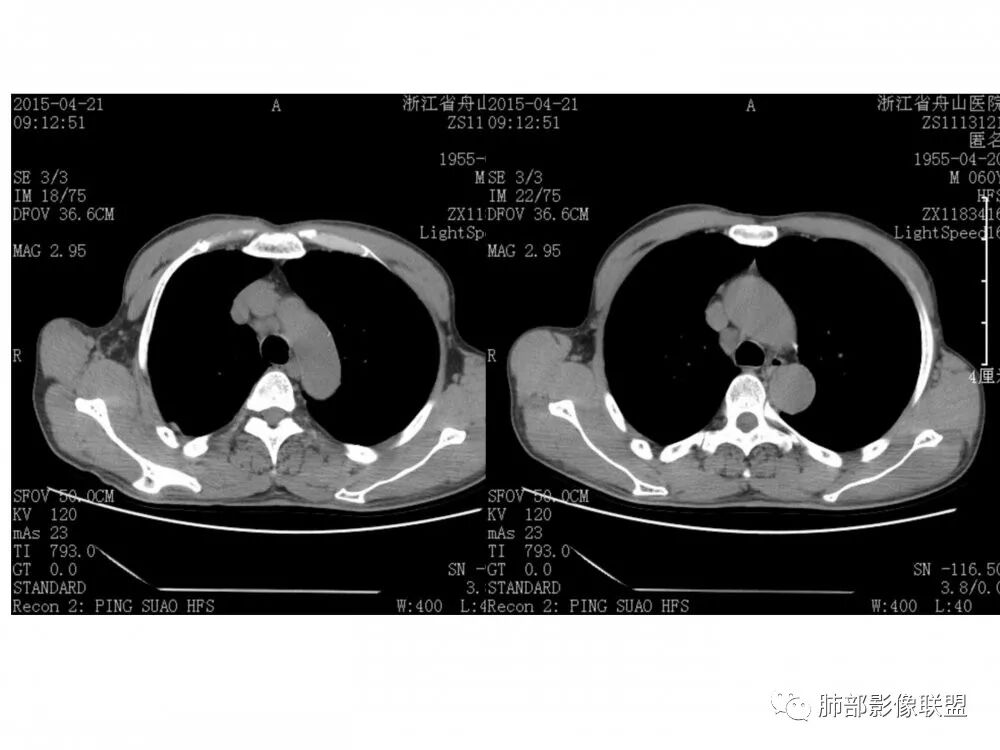

老年男性,60岁,右下肺门肿块,右下支气管粘膜下生长,并堵塞,无明显阻塞性肺炎和肺不张,早期多发淋巴结转移,似不均匀强化。综合看恶性程度高,考虑大细胞癌,一个不支持点,大细胞癌外周多见。

老年男性,右下基底外压狭窄,11、10、7、4、2组淋巴结肿大,考虑小细胞

老年男性,右下支气管新生物,像粘膜下生长,气管软骨似乎破坏不明显,无阻塞性炎症,纵隔淋巴结肿大;考虑恶性并淋巴结转移可能。

右肺下叶基底段支气管旁结节,低强化,支气管受压变窄,软骨连续未见破坏,右肺门及纵隔多发淋巴结增大,低强化与结节强化一致,考虑小细胞肺癌可能

右肺门结节,内见包埋血管,不均匀强化,长轴沿支气管且围绕支气管生长,支气管受压狭窄而未阻塞,肺门及纵隔见肿大淋巴结,老年男性,似有肺气肿背景,考虑恶性肿瘤性病变,首选小细胞肺癌

病理结果:鳞癌